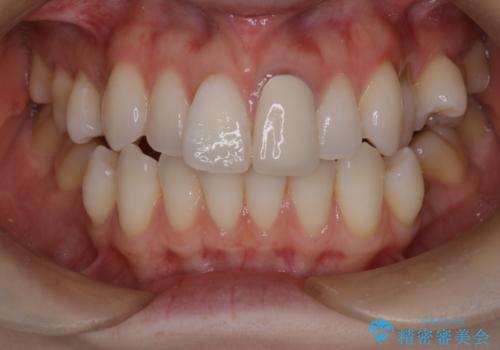

【重度叢生ワイヤー矯正】きれいな歯並びにしたい

骨格的3級傾向もあり、咬合関係を仕上げるのに時間がかかりましたが、患者様には大変満足していただけました。

難しいケースでしたが、矯正用アンカースクリューを用いながら、臼歯関係もきれいに仕上げることができました。